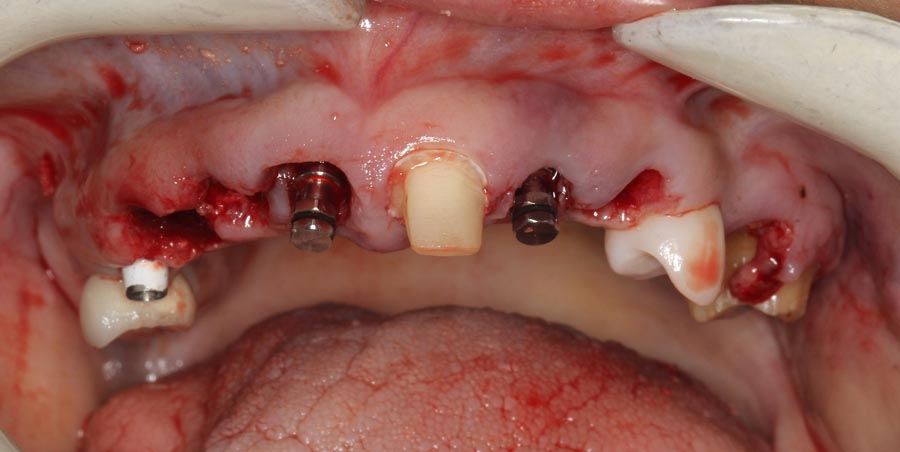

Smile GalleryImplant RestorationsFull Mouth Implant Restoration Full arch zirconia implant bridge (full smile) 1 of 37 Pre-op full smile Pre-op lips retracted Pre-op panoramic x-ray Extraction of strategic teeth Placement of implants Extraction of some remaining teeth after verification of adequate implant stability Occlusal view Post-op panoramic x-ray Immediately fabricated provisional restoration (tissue side view) Immediately fabricated provisional restoration (occlusal side view) Immediate provisional delivered on day of surgery Immediate provisional 2 weeks later Scalloped tissue developed from the provisional at 2 weeks Jig used for making a master impression Provisional in place (full smile) Provisional in place (lips retracted) Provisional in place (right side) Provisional in place (left side) Wax try-in (full smile) Wax try-in (right side full smile) Wax try-in (left side full smile) Wax try-in (full face, lips together) Wax try-in (full smile) Wax try-in (right side) Wax try-in (left side) Wax try-in (lips retracted) Full arch zirconia implant bridge on master cast (frontal view) Full arch zirconia implant bridge on master cast (occlusal view) Implant positions and soft tissue representation on master cast (occlusal view) Soft tissue representation on master cast (frontal view) Full arch zirconia implant bridge (tissue side view) Soft tissues on day of delivery (occlusal view) Soft tissues on day of delivery (frontal view) Full arch zirconia implant bridge delivered (lips retracted) Full arch zirconia implant bridge (lips retracted, close up) Post treatment panoramic x-ray Full arch zirconia implant bridge (full smile)